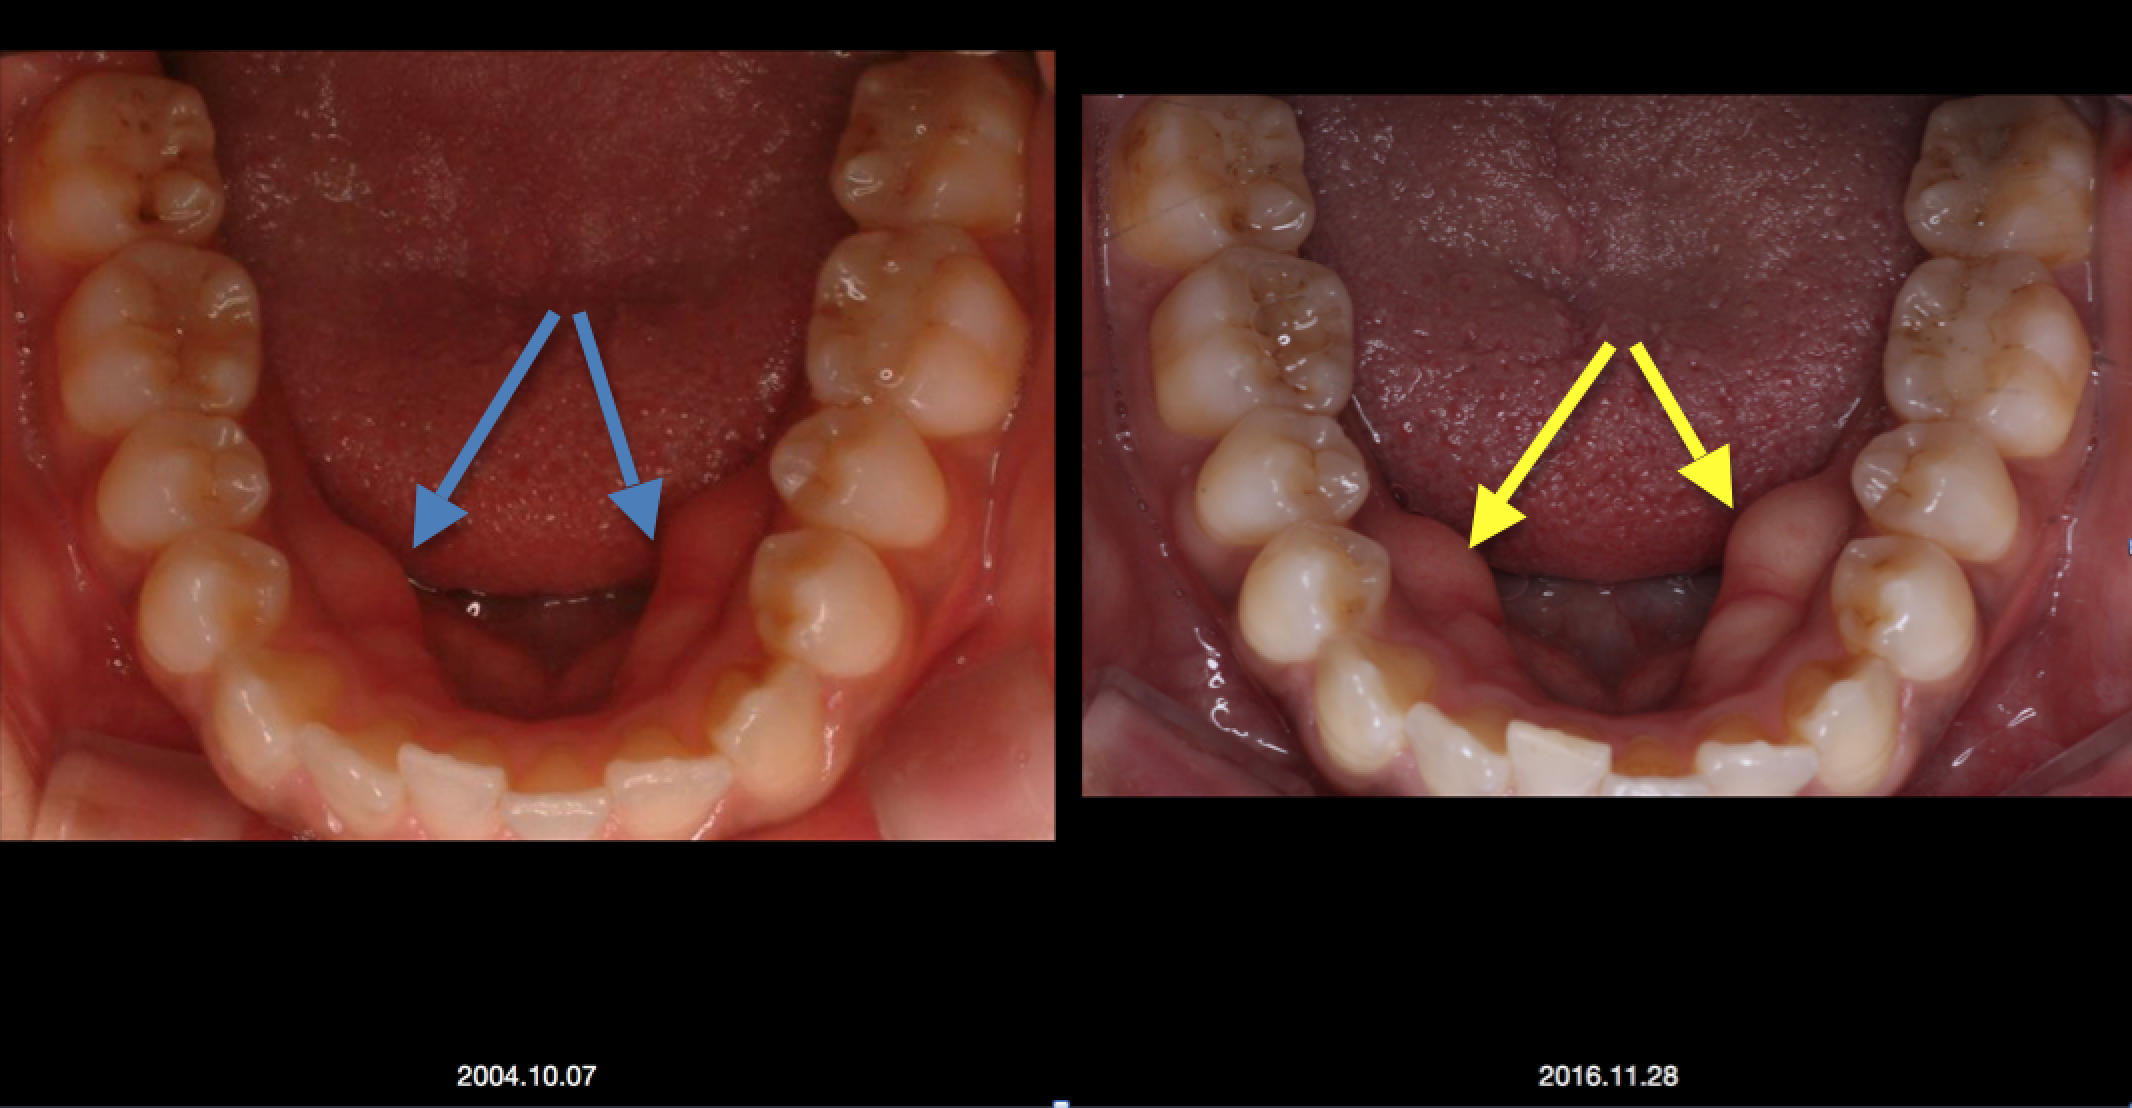

2016年に来院された時に撮影していたお口の中の写真を12年前の写真と比較すると、下顎の内側の骨の隆起が大きくなって発達してきています。これは噛み締めの習慣のある患者さんによく見られる現象です。